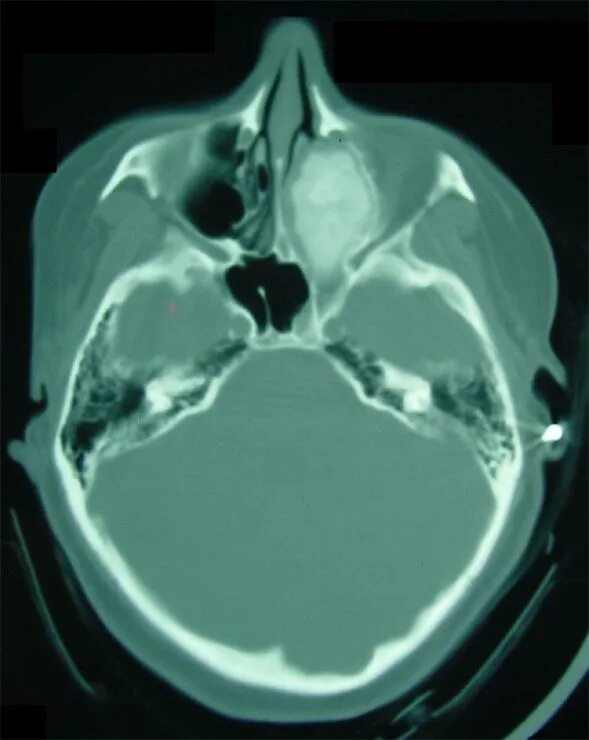

Фиброма кт